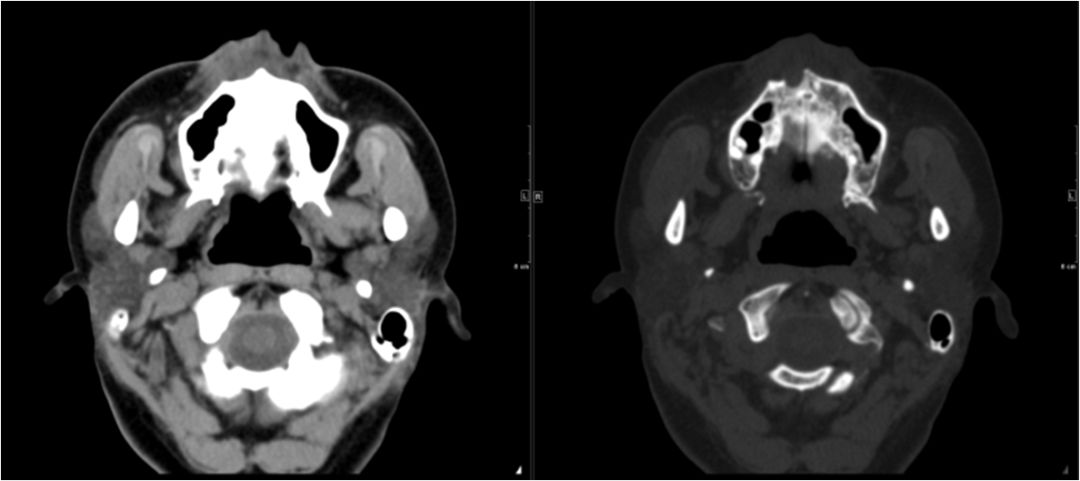

03 眶下间隙、颊间隙、咀嚼肌间隙、翼颌间隙

男,41岁,4天前右上后牙疼痛,右侧面部肿胀3天余。